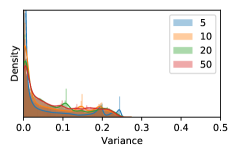

5.1 Distribution of Uncertainty Scores

Distribution of Uncertainty Scores Across Different Severity Levels As explained in Section 3, each uncertainty metric essentially defines an order/ranking among the data points. We conducted an analysis to better understand what data will be assigned high uncertainty under a particular uncertainty metric . Picking out the highest ranked data points (), we calculated the ratio of data points from each SL. Figure 4 summarizes the results as box plots for the Kaggle-DR and the Messidor-2 datasets; additional detailed statistics can be found in Table S.1 in the supplementary materials. From the plot and table, SL1 & SL2 examples account for a higher proportion among the top-ranked uncertain examples across the three ensemble methods. This finding matches our intuition that incipient disease examples (SL1 & SL2) are more likely to be considered uncertain by ensemble methods due to their ambiguity.

Comparing the three ensemble methods in Figure 4, the stacking ensemble method has the highest ratios of SL1 & SL2 data among the high-uncertainty examples it identified under both mean and var. TTA showed slightly better performance than MC-dropout but still falls behind the stacking ensemble method. Considering the fact that SL0 examples accounted for the majority of the dataset, the stacking ensemble method was much more precise (specific) in selecting truly ambiguous data points that were difficult to classify. From Figure 3, we can also see that the stacking ensemble method greatly outperformed the other two methods in finding false negatives under both mean and var uncertainty metrics.

In contrast, the MC-dropout method showed the worst overall performance among the three, as it can be seen from the high ratios of SL0 examples among the uncertain negatives in Figure 4. The histograms in Figure 2 provides another perspective to look into the phenomenon, where a decent proportion of MC-dropout model’s predictions on SL0 inputs entailed low confidence (far from 0 or 1), which from another angle explained why MC-dropout was less specific in terms of lower FNP; many no-DR inputs (i.e. SL0) were erroneously assigned high uncertainty by MC-dropout models.

As discussed in Section 5.1 and Section 5.3 in the main paper, the mean metric and the stacking ensemble will have better performance in the precision (specificity) on the ambiguous data. Here, more detailed results are shown in Figures S.3 & S.6 and Table S.1. Figures S.3 & S.4 show the histograms of the uncertainty score for Kaggle-DR and Messidor-2 datasets that are the in-distribution (i.d.) dataset in our experiment and FigureS.5 & S.6 show the histograms for ImageNet and CIFAR-10 datasets, which is the o.o.d. datasets in our experiment. Each group of histograms contains results from the three evaluated ensemble methods (stacking ensemble, MC-dropout and TTA) and the three uncertainty metrics (mean, var and kl). Additional detailed results not displayed in Figure 4 can be found in Table S.1, which shows the proportion of the data of different SLs varies across different . For comparison, we also included in Table S.1 the results from single learners, and the proportions of data of different SLs (before any selection was made).